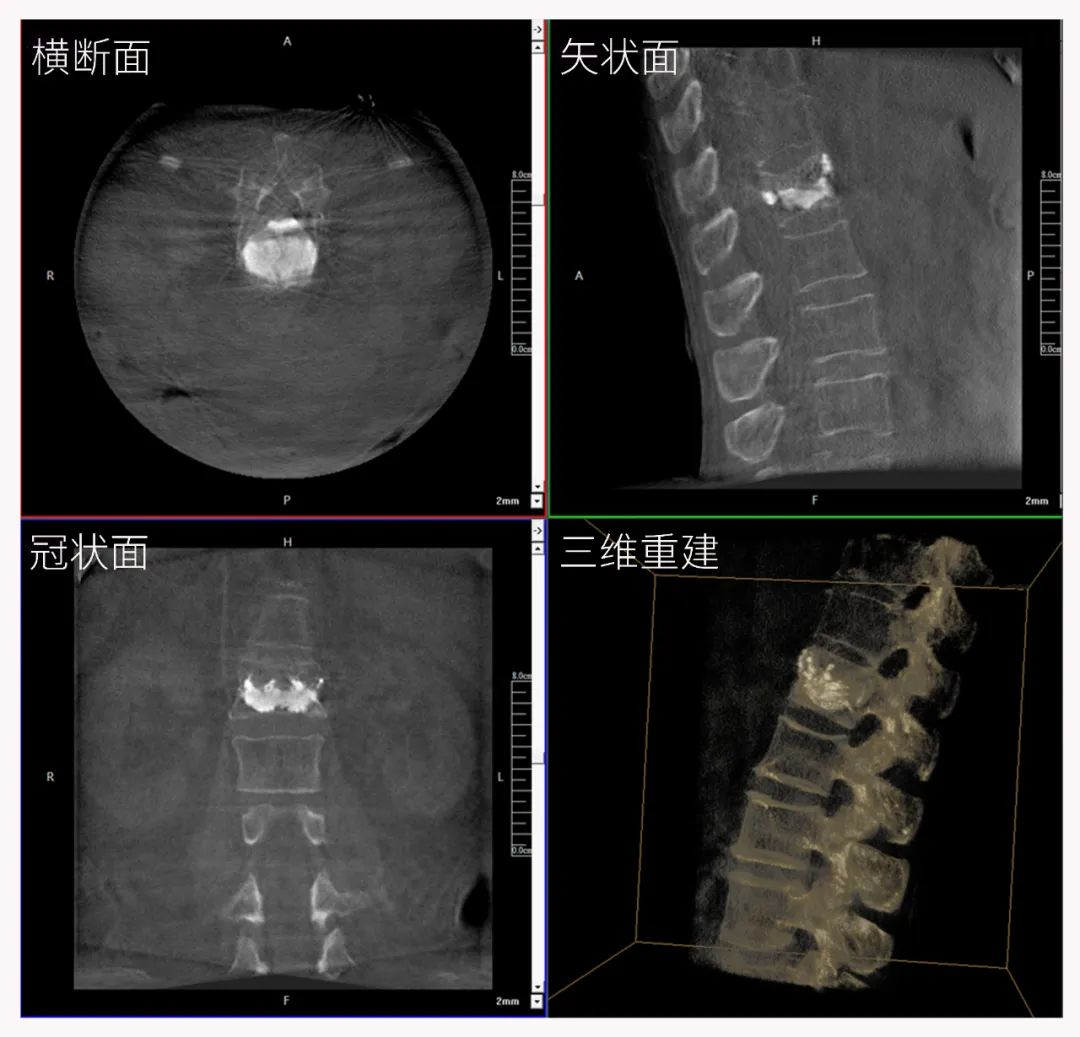

三维C形臂也被称为“术中CT”,它具备二维C形臂的全部功能。此外,它还具备三维成像功能,三维C形臂旋转采集多角度的二维投影数据,再通过计算机进行三维重建,能够生成横断面、矢状面、冠状面断层图像以及三维立体图像,提供更全面、更立体的解剖学信息。

二维正侧位影像

三维“类CT”影像

二维C形臂提供的影像存在固有局限性,其成像原理是基于单一方位的投影,导致深部解剖结构信息缺失,且容易受到骨骼和组织的重叠干扰,使得部分病灶难以清晰显示,甚至被掩盖。相比之下,三维C形臂通过三维重建技术,可以获得类似CT的断层扫描图像,从而解决了二维影像的重叠问题。

医生能够利用这些三维图像,更直观、更深入地分析病变,进行全方位观察,例如:精确评估骨折复位情况、清晰显示内植入物的位置及其与周围组织的关系等。尤其在复杂骨折、脊柱手术、呼吸介入等临床场景中,三维C形臂提供的详细信息对手术导航和疗效评估至关重要。